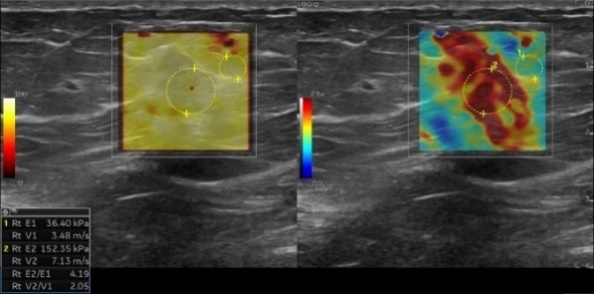

美國(guó)GE LOGIQ E11 彩超 的全新技術(shù)

1.全模态彈性成像技術(shù)

應力式彈性成像和複合剪切波彈性可(kě)應用于腹部、淺表、婦科、泌尿、兒科等領域,對于慢(màn)性病的評估、腫瘤良惡性鑒别、癌前病變的早期判定、損傷評估等疾病有重要的臨床意義。